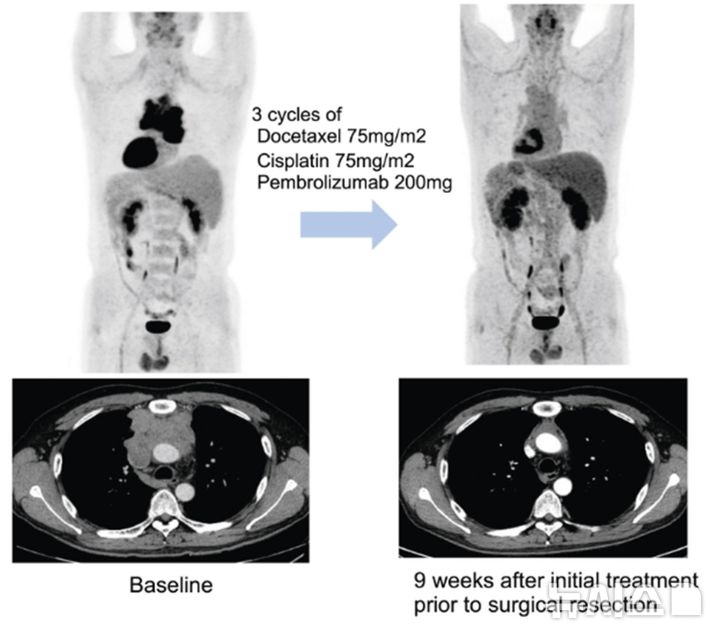

[서울=뉴시스] 수술에 앞서 3주 간격으로 세 차례 항암화학요법에 면역항암제 펨브롤리주맙을 병용 투여한 결과병리학적으로 완전 관해를 보인 환자 예시. 이 환자는 3기 흉선암이었으나 현재 3년 이상 재발 없이 경과 관찰 중이다. (사진= 삼성서울병원 제공)

연구팀은 이들 환자에게 3주 간격으로 세 번에 걸쳐 기존 항암화학요법에 펨브롤리주맙을 병용 투여한 다음 수술 가능 여부를 평가했다.